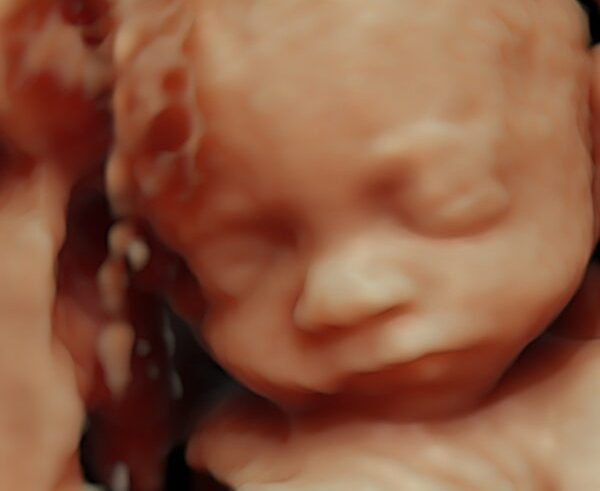

Een 3D/4D HD live echo is alsof je een kijkje neemt in de buik. Bij Baby’s World is het mogelijk om een vroege 3/4D pretecho te maken tussen 13 en 19 weken zwangerschap. Vanaf 20 – 34 weken zwangerschap is het mogelijk om het gezicht van jouw kindje goed in beeld te krijgen met een 3/4D pretecho. De beste periode is tussen de 24 en 30 weken zwangerschap.